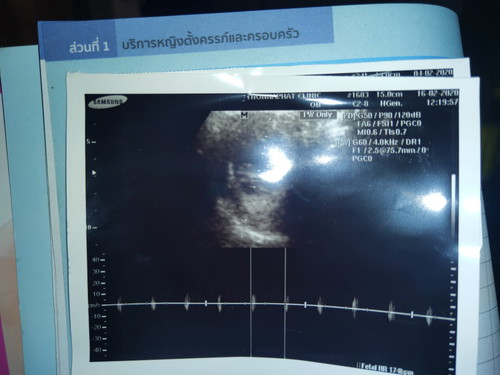

ซาวตอน 8w5d ระยะการเต้นของหัวใจในใบซาวคือปกติมั้ยค่ะ แม่ๆท่านไหนพอจะทราบบ้างมั้ยค่ะ